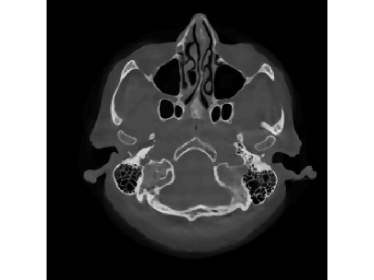

Finally, we apply the proposed method on a clinical head dataset. The data are acquired with a Siemens Artis zee angiographic C-arm system (Siemens Healthcare GmbH, Forchheim, Germany). In this experiment, we choose one slice of a 3D clinical head dataset as the ground truth image (Fig.9) and reproject it to simulate the acquired sinogram data in the fan-beam system with the following trajectory parameters: the source-to-isocenter distance is 750 mm and isocenter-to-detector distance is 450 mm. The angular step is 1 degree and the total scan range is 360 degrees. The equal-spaced detector length is 620 mm with the pixel length 111 mm.

The full projections are shown in Fig.10. When the detection range κ𝜅\kappa is limited, there could be saturation for the projection. In Fig.10 and Fig.10, observations for κ=0.6pmax𝜅0.6subscript𝑝\kappa=0.6p_{\max} and κ=0.4pmax𝜅0.4subscript𝑝\kappa=0.4p_{\max} are displayed, respectively. Our task is to recover the image from the saturated projections via M1bit-CS-ISD. The results are compared with FBP and SART, two standard CT reconduction frameworks. For FBP, we apply the modification given by [38] that utilizes water cylinder extrapolation to remedy missing projections caused by truncation or overexposure. For SART, one can remove those saturated projections when they are found, for which the ISD can be used as well. We denote this method as SART-ISD, of which the detection scheme is as the same as M1bit-CSR-ISD but SART is used as the reconstruction method.

Figure 9: Reconstruction results for the clinical data (κ=0.6pmax𝜅0.6subscript𝑝\kappa=0.6p_{\max}): (a) ground truth; (b) FBP-WCE; (c) SART-ISD; (d) M1bit-CSR-ISD.

For κ=0.6pmax𝜅0.6subscript𝑝\kappa=0.6p_{\max}, the reconstruction results of FBP-WCE and SART-ISD are given in Fig.9 and 9, respectively. As shown before, the traditional FBP method cannot handle the saturated data. With water cylinder extrapolation, the reconstruction quality has been improved but loss of clear patient boundaries still happens. The overall performance of SART-ISD is slightly better than FBP-WCE but capping artifact can be identified at the object border. Further improvement is obtained using the proposed M1Bit-CSR-ISD to acquire information from the saturated data. As shown in Fig.9, most of outer boundaries are nicely restored and streaking artifacts are effectively eliminated.